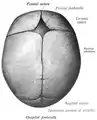

La suture sagittale (ou suture bipariétale ou suture interpariétale ou suture pariétale ou suture rhabdoïde) est la suture crânienne qui relie les bords supérieur des deux os pariétaux.

Elle présente deux repères anatomiques : le bregma formé par son intersection avec la suture coronale, et le vertex du crâne.

La suture sagittale